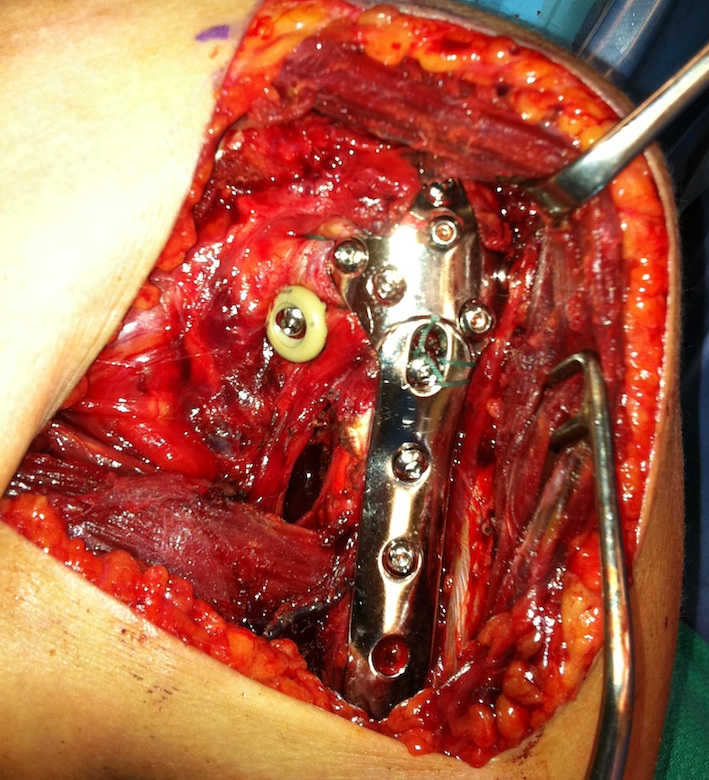

proximal humerus fracture Background ORIF with locking plate Arthroplasty Greater tuberosity fractures Lesser tuberosity fractures / avulsions Book traversal links for Proximal humerus fractures ‹ Pectoralis Major Tears Up Background ›